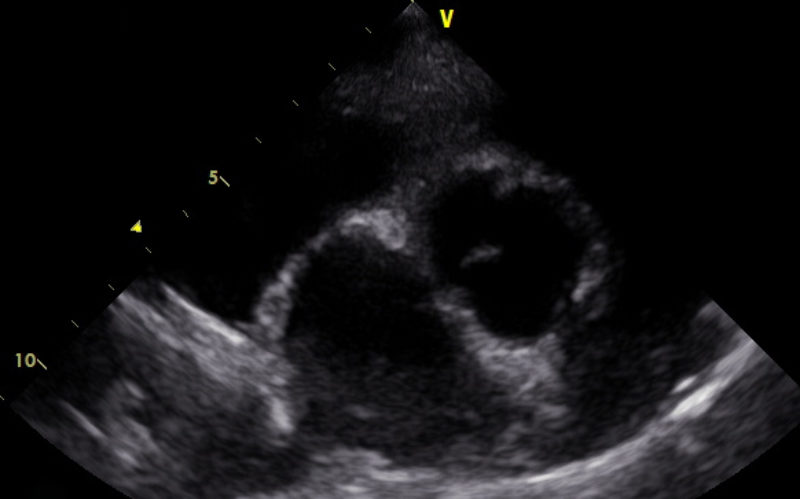

Es gibt verschiedene Ursachen für diese Form der Arrhythmie, welche mit Hilfe einer Echokardiographie weiter abgeklärt werden können. Daher wurde dem Besitzer als nächster diagnostischer Schritt ein Herzultraschall angeraten. Hierfür liegt der Hund auf einem speziellen Tisch und wird in rechter und linker Seitenlage geschallt. Im Herzultraschall zeigte sich in den Phasen, in denen „Astor“ die Rhythmusstörung hatte, eine stark verminderte Pumpleistung des linken Ventrikels mit einem subjektiv vergrößerten linken Herz (Hauptkammer und Vorkammer). Was sich dann auch in den Messwerten bestätigte. In Phasen, in denen der Herzschlag einen normalen Rhythmus hatte, war die Pumpleistung etwas besser, die Messwerte lagen im Graubereich. Der linke Vorhof war leicht vergrößert. Neoplasien oder Veränderungen im Herzmuskel konnten nicht dargestellt werden.